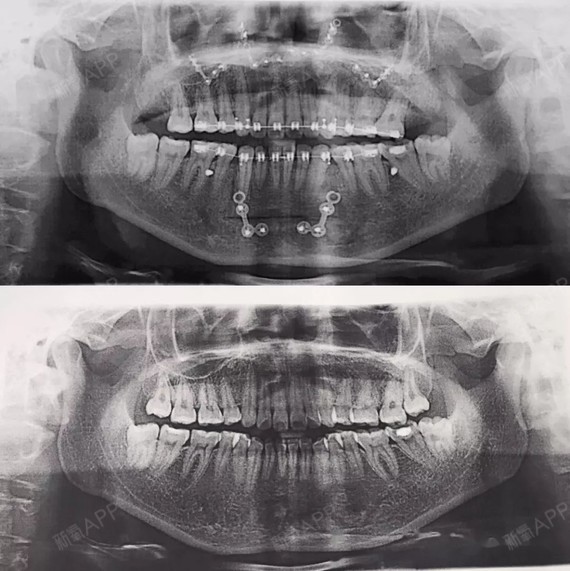

下巴后缩x光

下颌后缩

矫正前后x光片对比